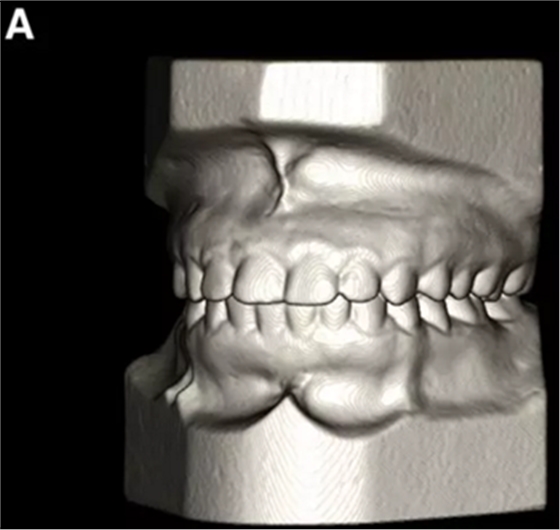

患者的上頜骨和下頜骨研究模型在最大牙尖交錯位時確定和數(shù)字化(圖2,A),作為咬合指導(咬合指導)。該數(shù)字化咬合指導在齦緣周圍進行數(shù)字化修剪,以便在CBCT掃描上可以更好得可視化(圖2,B)。

圖2. A,咬合時對象研究模型的右側(cè)舌側(cè)視圖掃描將作為未來指導;該指導稍后用于將懸浮的下頜骨配對到修剪的上頜骨;B,左側(cè)舌側(cè)視圖的數(shù)字化修整牙合引導。